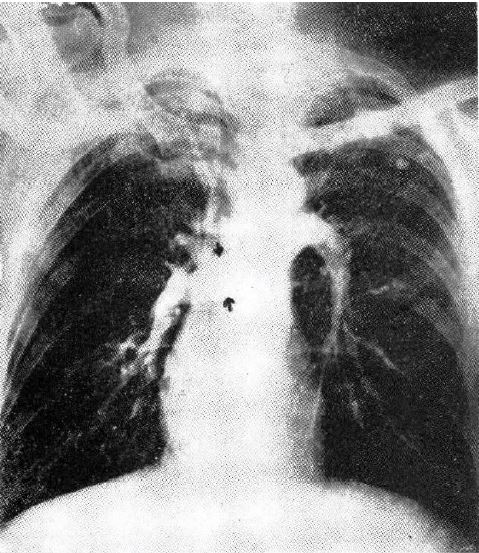

Visualization of the Chambers of the Heart, the Pulmonary Circulation, and the Great Blood Vessels in Man – A Practical Method

ヒトの心腔,肺循環,大血管造影-実践的方法について

George P. Robb, Israel Steinberg. American Journal of Roentgenology and Radium Therapy 41:1-17,1939

前掲のMonizらの報告後,右心腔・肺血管造影の試みはいくつかあったもののいずれも実験的なものにとどまっていた.初の本格的臨床応用は本論文の前年に発表されたCasellanosらの報告(Arch Soc Estud Clin 31:523-96,1937)であったが,対象は小児の先天性疾患に限られ,左心系については論じられていない.成人の左心系をふくめて,初めて実際的な心腔造影を報告したのが本論文である.ここではカテーテルを使用せず,肘静脈からの静注である.造影剤は有機ヨード造影剤のダイオドラストを用いている.症例数は127例(238回)で,循環時間を推測してのいわゆる「一発撮り」 であるが,具体的な位置決め方法や撮影のコツを含めてきわめて詳細,実際的な記述である.